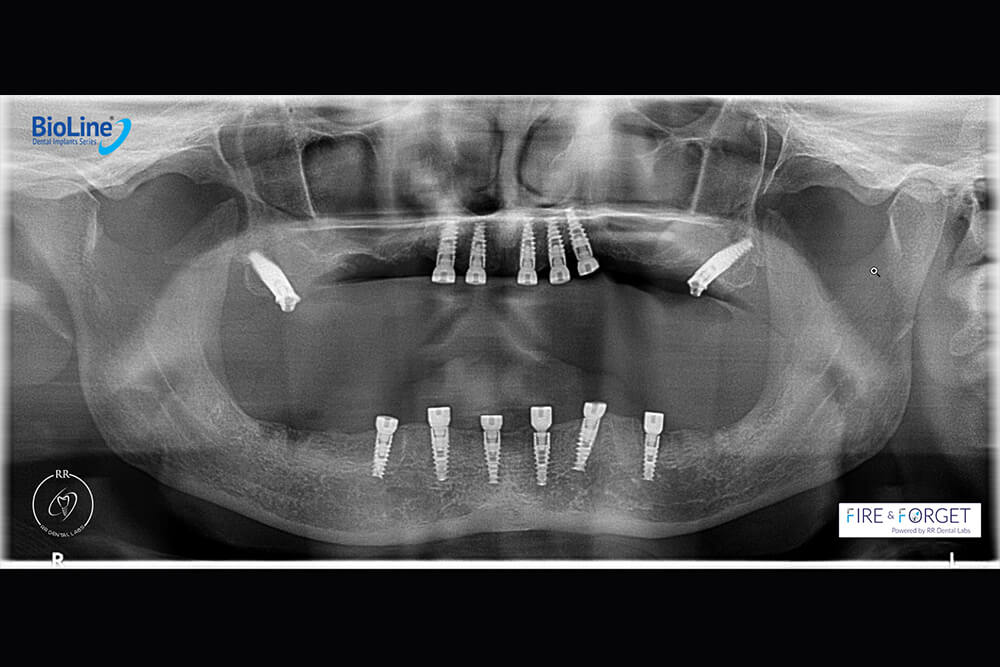

Case 47